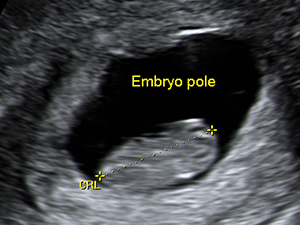

The crown-rump length of the embryo at 9 weeks

The crown-rump length of the fetus at 12 weeks